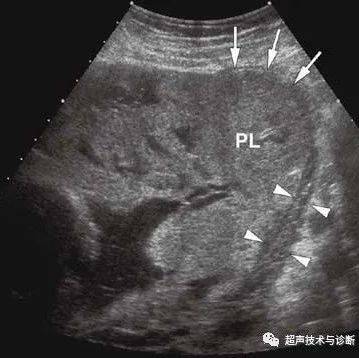

由于婴儿是剖腹产,因此病毒的所有潜在来源都保存完整。在胎膜破裂前,剖宫产期间收集羊水,并检测新冠病毒的E和S基因均为阳性。

研究人员发现,新冠病毒的浓度在胎盘中最高。